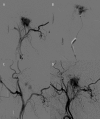

Case report: We report the endovascular approach to three patients harboring glomus jugulare paragangliomas. In all cases incomplete occlusion of the lesions was achieved and recanalization in the follow-up period was revealed. Two patients presented no clinical improvement and the remaining one experienced a transient withdrawal of tinnitus.

Conclusions: It is technically difficult to achieve complete obliteration of glomus jugulare tumors with the use of embolization and the subtotal occlusion poses a high risk of revascularization and is not beneficial in terms of alleviating clinical symptoms.